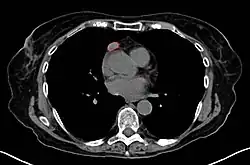

Imaging

A chest X-ray may identify widening of the mediastinum suggestive of thymoma, but computed tomography or magnetic resonance imaging (MRI) are more sensitive ways to identify thymomas and are generally done for this reason.[68] MRI of the cranium and orbits may also be performed to exclude compressive and inflammatory lesions of the cranial nerves and ocular muscles.[69]

As thymomas are seen in 10% of all people with the MG, they are often given a chest X-ray and CT scan to evaluate their need for surgical removal of their thymus glands and any cancerous tissue that may be present.[24][67] Even if surgery is performed to remove a thymoma, it generally does not lead to the remission of MG.[102] Surgery in the case of MG involves the removal of the thymus, although in 2013, no clear benefit was indicated except in the presence of a thymoma.[109] A 2016 randomized, controlled trial, however, found some benefits.[110]